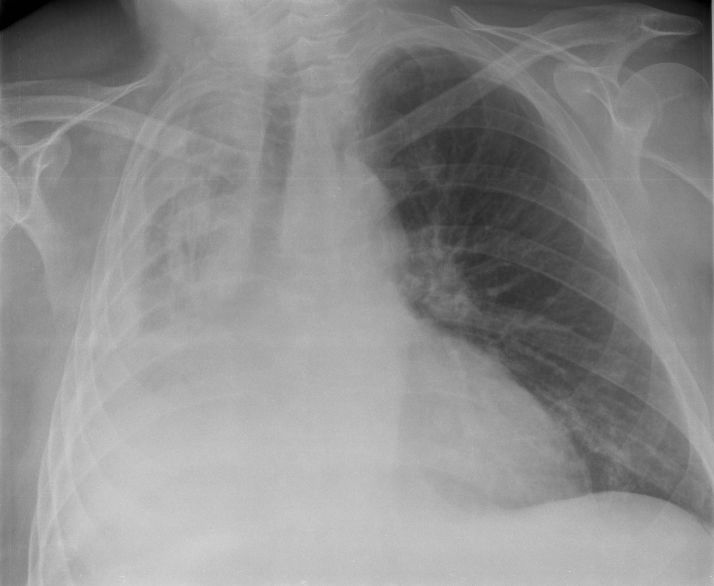

INTERPRETACIÓN RADIOGRÁFICA DEL TÓRAX EN RECIÉN NACIDOS

RAYOS X

Torax En Neonatologia 5 638 (image/jpeg)

Sistematización de lectura

Tejidos blandos

Tejido óseo

Diafragma

Pleura

Cisuras Pulmonares

Mediastino

Timo

Der. es 1.5 cm más alto

Se visualiza en neonatos y niños < 2 años

Corazón

IC= 0.57 (0.53 a 0.57)

Hilio y vasos pulmonares

Parénquima pulmonar

Confirmación de Patología

ATELECTASIA

ENFERMEDAD MEMBRANA HIALINA

SDR

NEUMONÍA

NEUMOTÓRAX

DERRAME PLEURAL